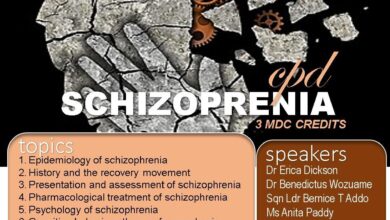

3 CPD Points On Schizophrenia By 37 Military Hospital

The 37 Military Hospital is organizing a CPD tomorrow this, 18th September. It’s a paid CPD. Hence interested person has…